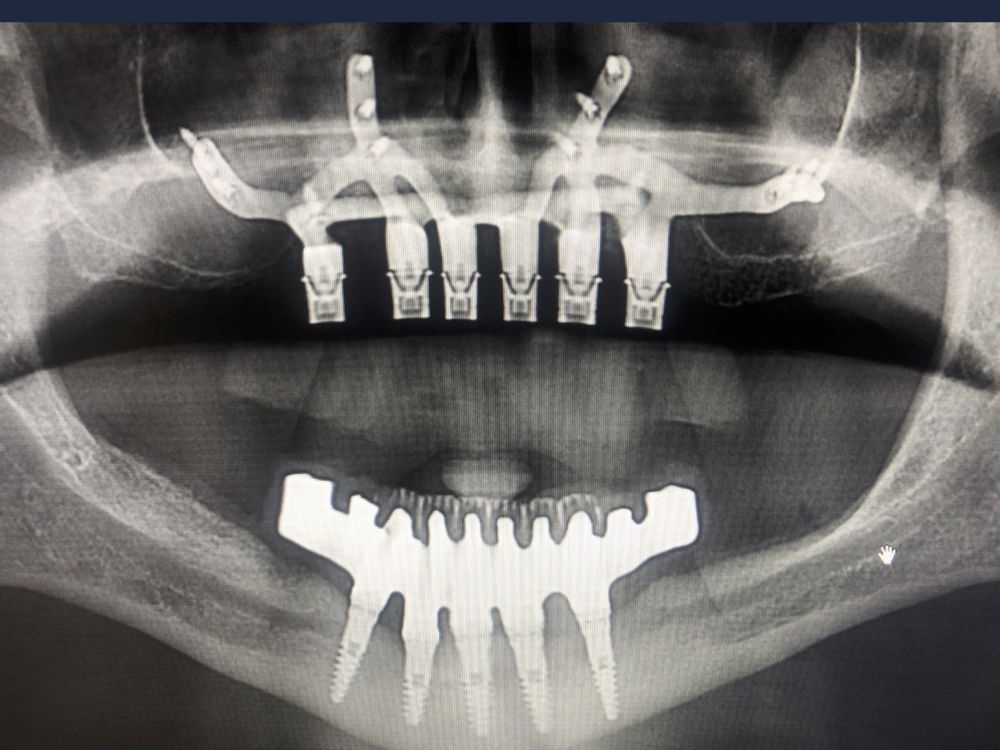

Clinical Case: A subperiosteal sintered titanium structure was fabricated with six transepithelial connections that were rehabilitated with an immediate implant supported fixed prosthesis made of PMMA. Two months later, a sintered chromium-cobalt framework with machined bases covered with acrylic resin teeth was fabricated as the final restoration. At one year follow-up, the case remains stable.

Subperiosteal implants (SI) were developed in Sweden in the early 1940´s. The SI consisted of a custom-made implant, inserted under the periosteum and fixed with screws and the mucous tissue that covered it3,4. They were manufactured in chromium-cobalt or titanium alloys and were rehabilitated by transmucous pillars that emerged in the oral cavity5. Although they were used for years in cases of maxilla atrophies, they were replaced by endoosseous implants designed by Branemark6. This was due to its complex manufacturing. It was necessary to take an impression of the residual bone ridge, which was sent to the laboratory for the structure design, with the consequent imbalances since they were not very stable models. In this way, its placement in the patient was very difficult, and several complications could appear7,8. However, advances in the planning and manufacturing field with various materials have allowed these structures to be made digitally with an excellent predictability and fit, thus avoiding more complex surgeries9.